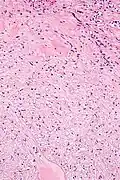

| Micrograph of a renal medullary fibroma (bottom of image). Renal tubules are seen at the top of the image. H&E stain. | |

They consist of bland spindle-shaped or stellate-shaped cells in a loose stroma. Renal tubules may be entrapped.